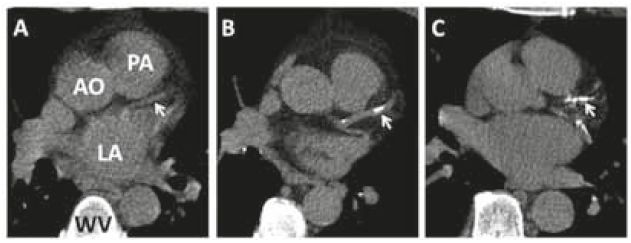

De CT-calciumscore is een relatief recente tweedelijnstechniek voor de analyse van coronairlijden.

Detectie coronairsclerose